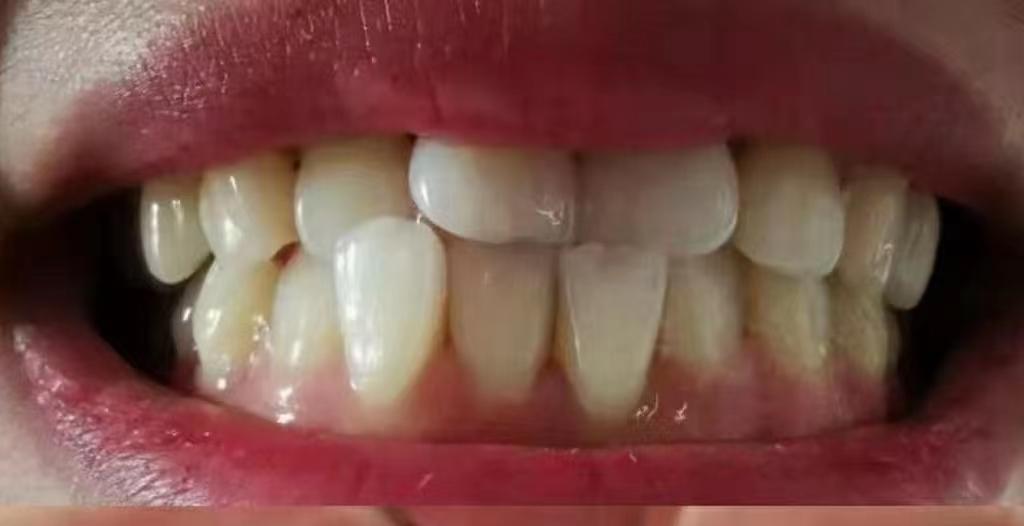

平時(shí)我們看到的自己牙齒可能這樣

看起來好像也還行

但你從牙醫(yī)視角看過自己的牙嗎!

就這兩顆自由飛翔的大門牙~能不影響咱的顏值嗎